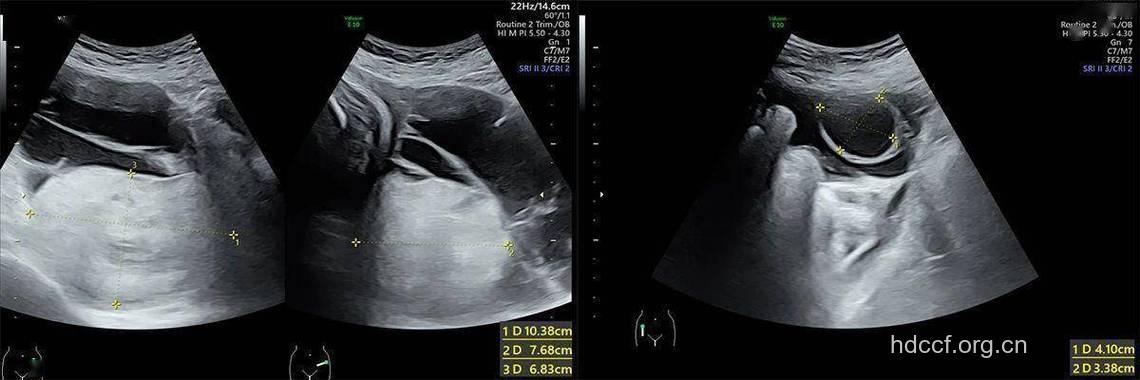

专家表示,只有少数经常体检的人才能够早期发现,“有个不孕的病人,一直做B超监测排卵,结果就发现卵巢逐渐增大到七八厘米,而且不缩小,后来手术发现是早期,能够早期发现就很好”。

专家建议,为保险起见,B超最好是阴超、腹超都做,阴超对存在于盆底的卵巢肿瘤看得比较清楚,活动到腹部上面的肿瘤就要靠腹部B超检查。建议B超在月经期刚结束时做,那时不会排卵,最好是月经结束两三天时做比较准。“经常有病人拿着B超单来咨询,卵巢囊肿大概两三厘米就很紧张,有时候其实就是一个排卵的卵泡,或者是排卵以后形成一个黄体,这个时候就容易跟卵巢肿瘤区别不开”。